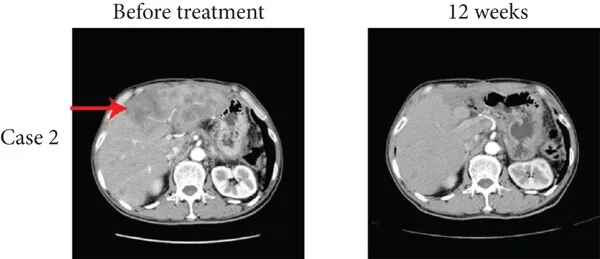

另一例为20岁男性肝转移患者,经12周TIL联合纳武利尤单抗治疗后,达到完全缓解(CR),肝转移灶消失(详见下图b),中位无进展生存期(PFS)为12.1个月。

▲图源“J Immunol Res”,版权归原作者所有,如无意中侵犯了知识产权,请联系我们删除